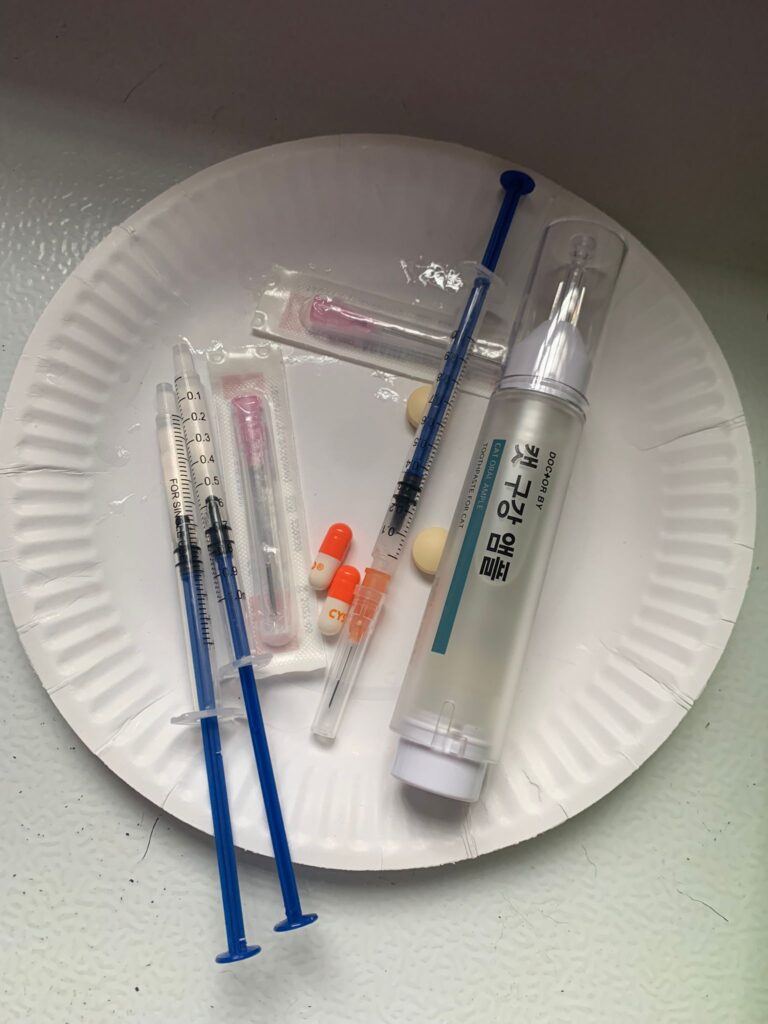

Prepare his fercosang jab to be given Tmr

11Am+: given Subcut, b com n b12 and fercosang. He is still on f patch, wipe his face

Morning: major cleaning day. Subcut him n given b12 b com jab. His f patch drop off le. Given bupre. Still love selar

Morning: got helper in to cut nails, steam bath and clean ears. She can handle him alone. Given Subcut bupre n put on f patch for him.

Morning: got 2 helpers in to clean up and for him: cut nails, clean ears and steam brush fur. His f patch if off, given Subcut and bupre jab

Morning; both eyes discharge look bad, clean up and put banocin on his ear. Will Subcut him and give Clav jab and bupre n put on new f patch for him

Morning: f patch intact. Apply banocin powder on ear. Still look got blood clog, didn’t bleed further. Given 5th and last Clav jab.

Morning: Subcut n on regular med and place new f patch n still given bupre

10am+: b4 I Subcut n give painkiller still eating ok. Subcut and given b12 b com bupre and put on a f patch (end 1.3.24)

11Am+: given bupre jab and place a f patch on his left ear.

12pm+: 4.12kg – gain 50g in 2 months. On regular maintenance Subcut and bupre n b12. and dental care

Morning: given doctorby toothpaste – he ok.

Morning: given him doctorby oral and bupre

Morning: given Subcut w b12 b com. N bupre

Morning: Subcut w b12 and Buprenophine

Morning: Subcut w b12 and Buprenophine

Morning: Subcut w b12 and bupre.